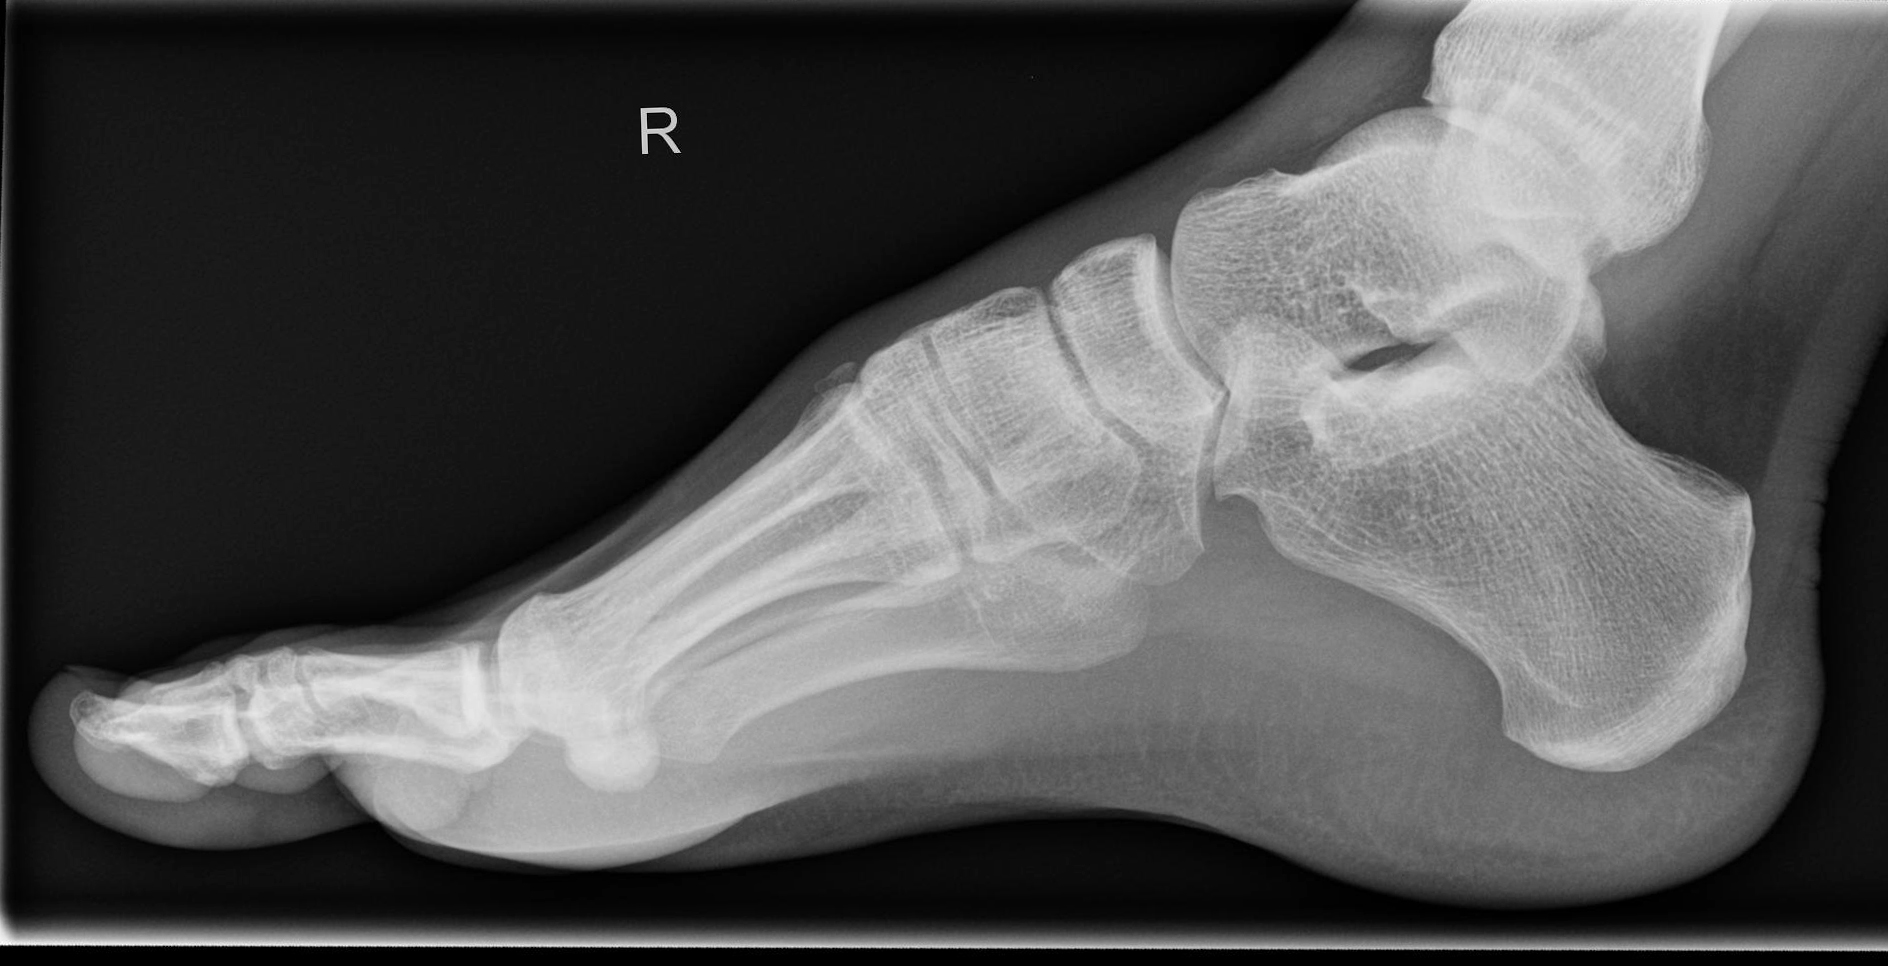

Fuß streng seitlich

Technik

• FDA: 1,05 m

• Ausgangsformat: 24/30 quer

• Übertischaufnahme

Metatarsalien decken sich an ihrer Basis, bei Verdacht auf Senkfuß eine Aufnahme im Stehen mit Belastung, d.h. gesundes Bein anheben, mit angestelltem Bildempfänger und horizontalem Strahlengang.

Lagerung

sitzend/ liegend auf Tisch

Innen- oder Außenseite aufliegend je nach Indikation

Fuß senkrecht zum Bildempfänger.

Zentralstrahl

senkrecht auf Objektmitte

Einblendung

gesamter Fuß einschließlich Ferse

Qualitätskriterien

Gut einsehbares oberes und unteres Sprunggelenk. Die Basen der Mittelfußknochen überlagern sich.